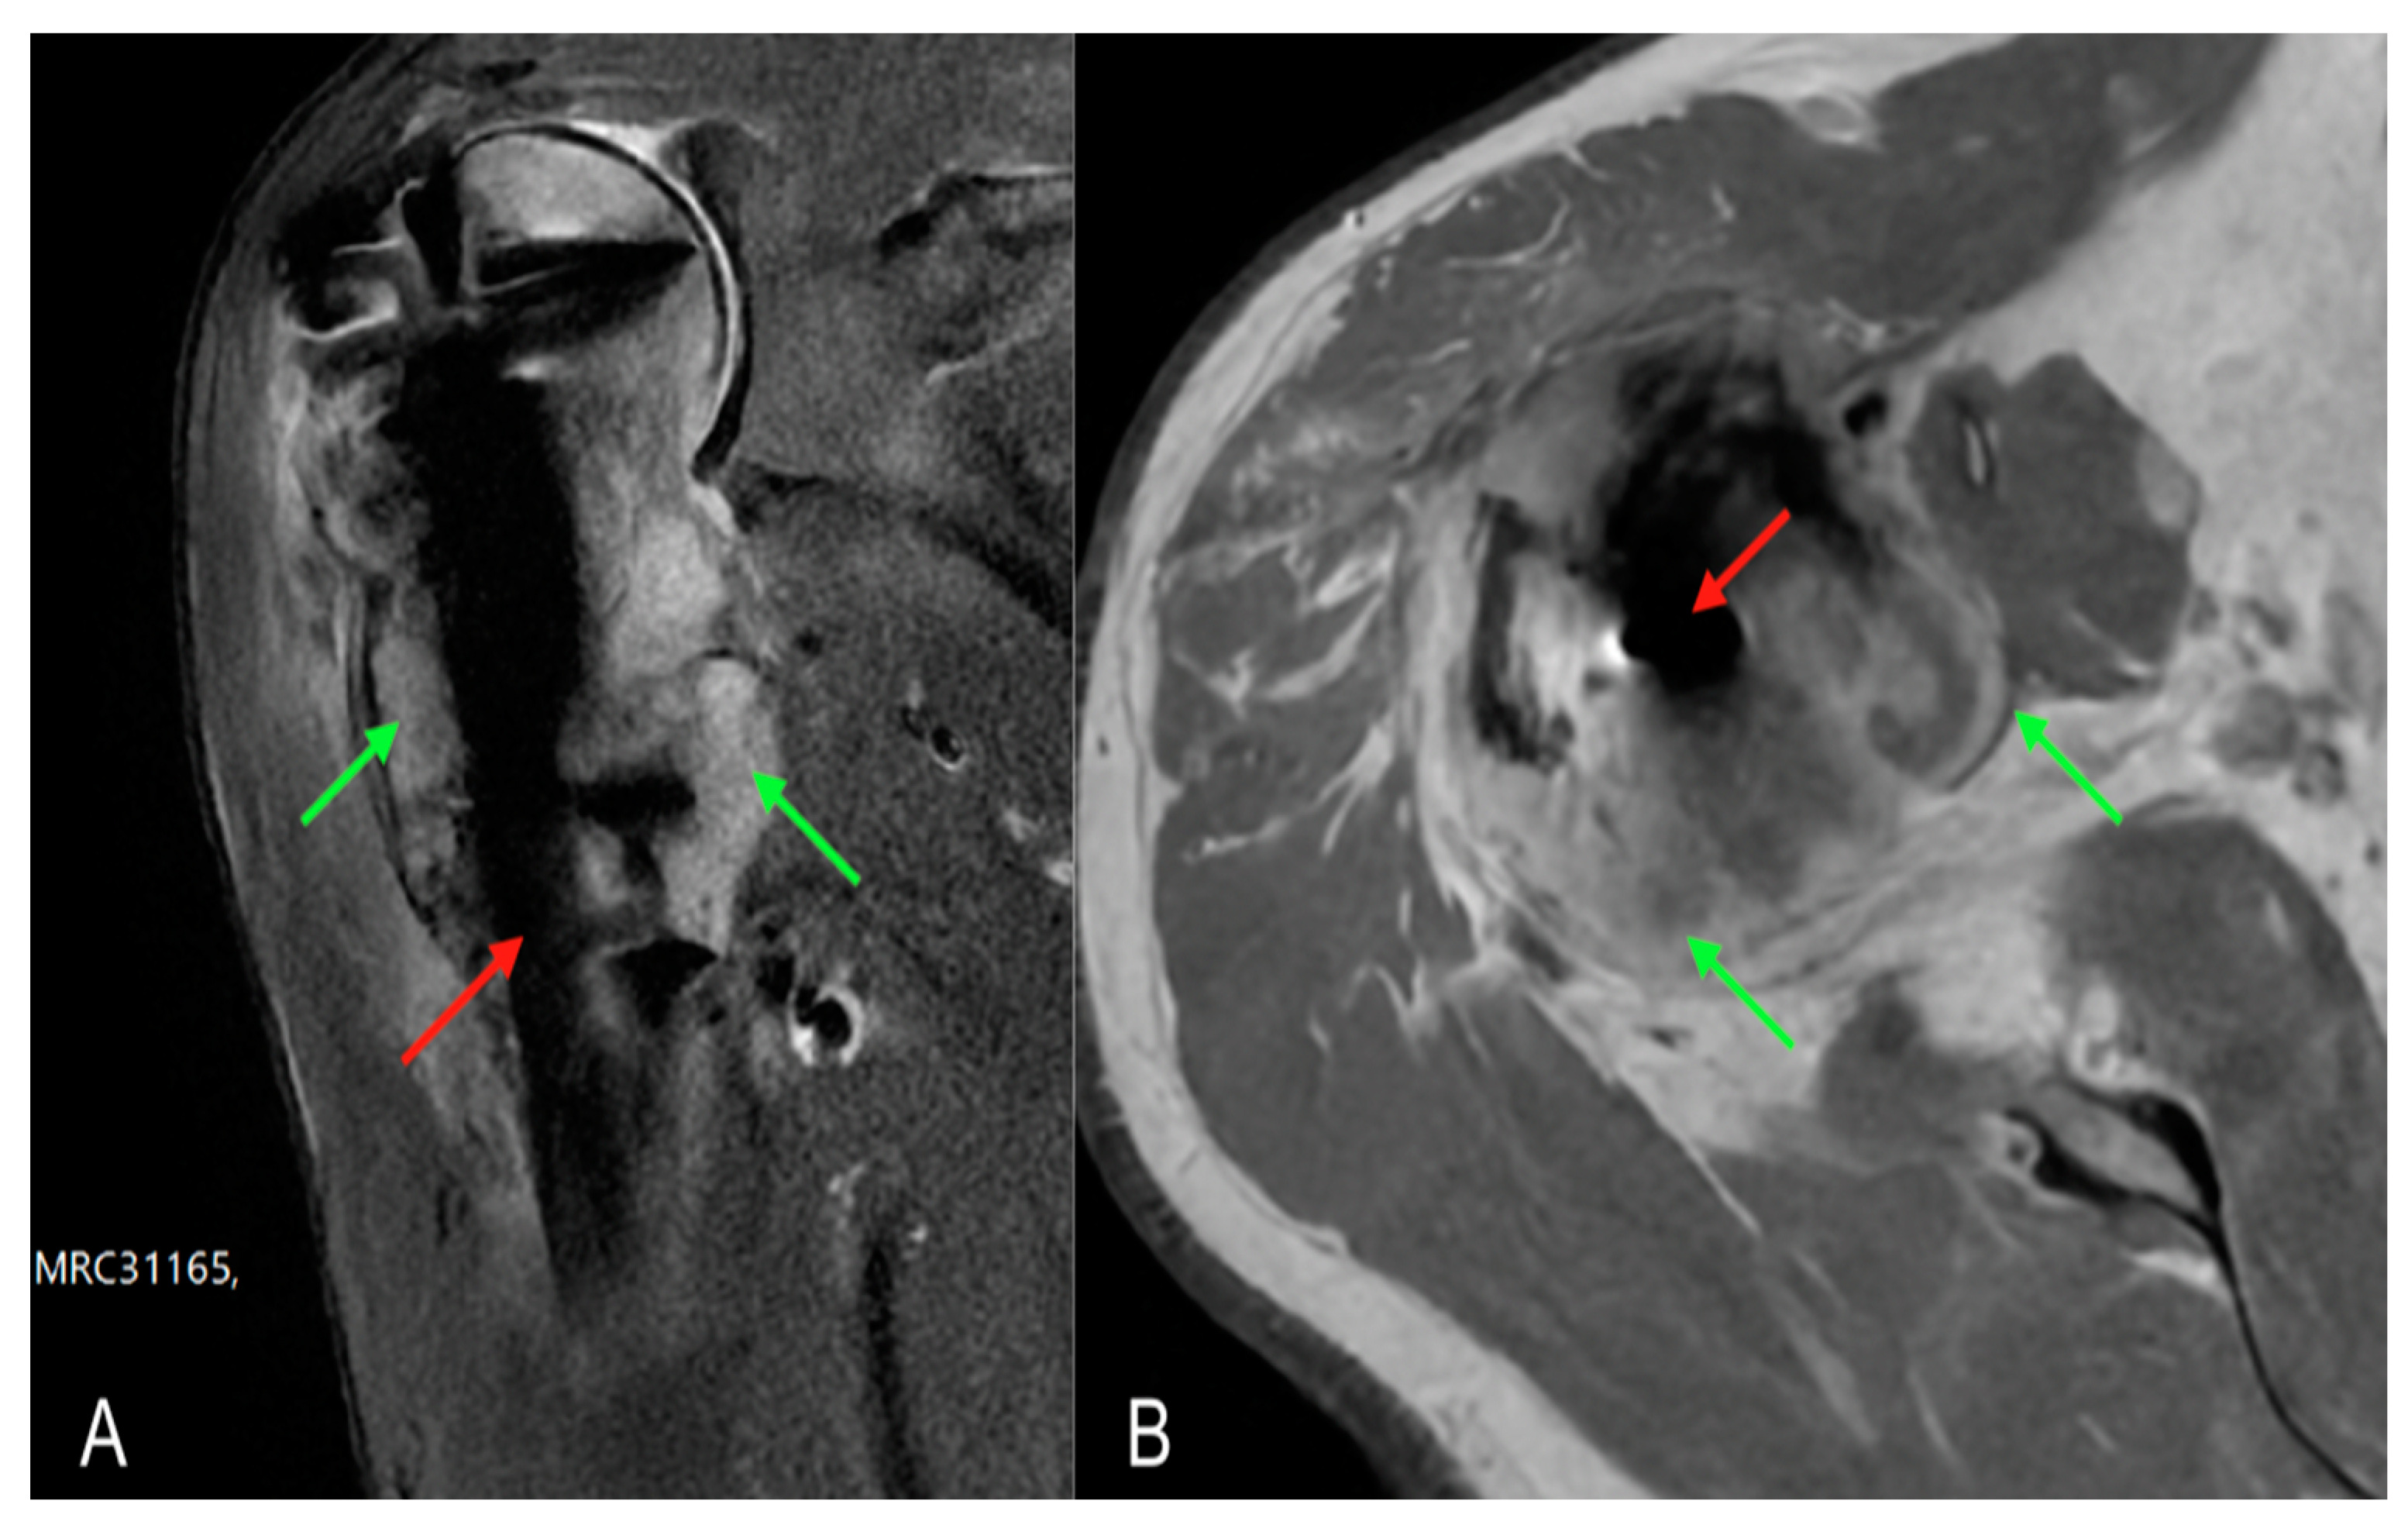

Given the suspicion of a neoplastic lesion, it was decided to carry out an in-depth diagnostic with an MRI examination to complete the local instrumental imaging which highlighted a subversion of a voluminous portion of tissue in the proximal III of the humerus with manifestation in the periskeletal soft tissues, compatible with a replacement lesion (Figure 3). S CT-guided biopsy was performed to realise histological examination.

Figure 3. MRI scans of the left arm showing intramedullary nail (red arrow) and periskeletal neoplastic pathological tissue (green arrows) at the level of the humeral head and diaphysis: (A) coronal MRI section; (B) transversal MRI section.